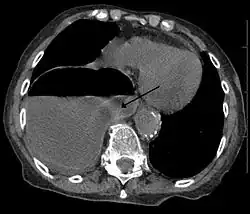

Diagnosis can be made by either CT or X-ray.